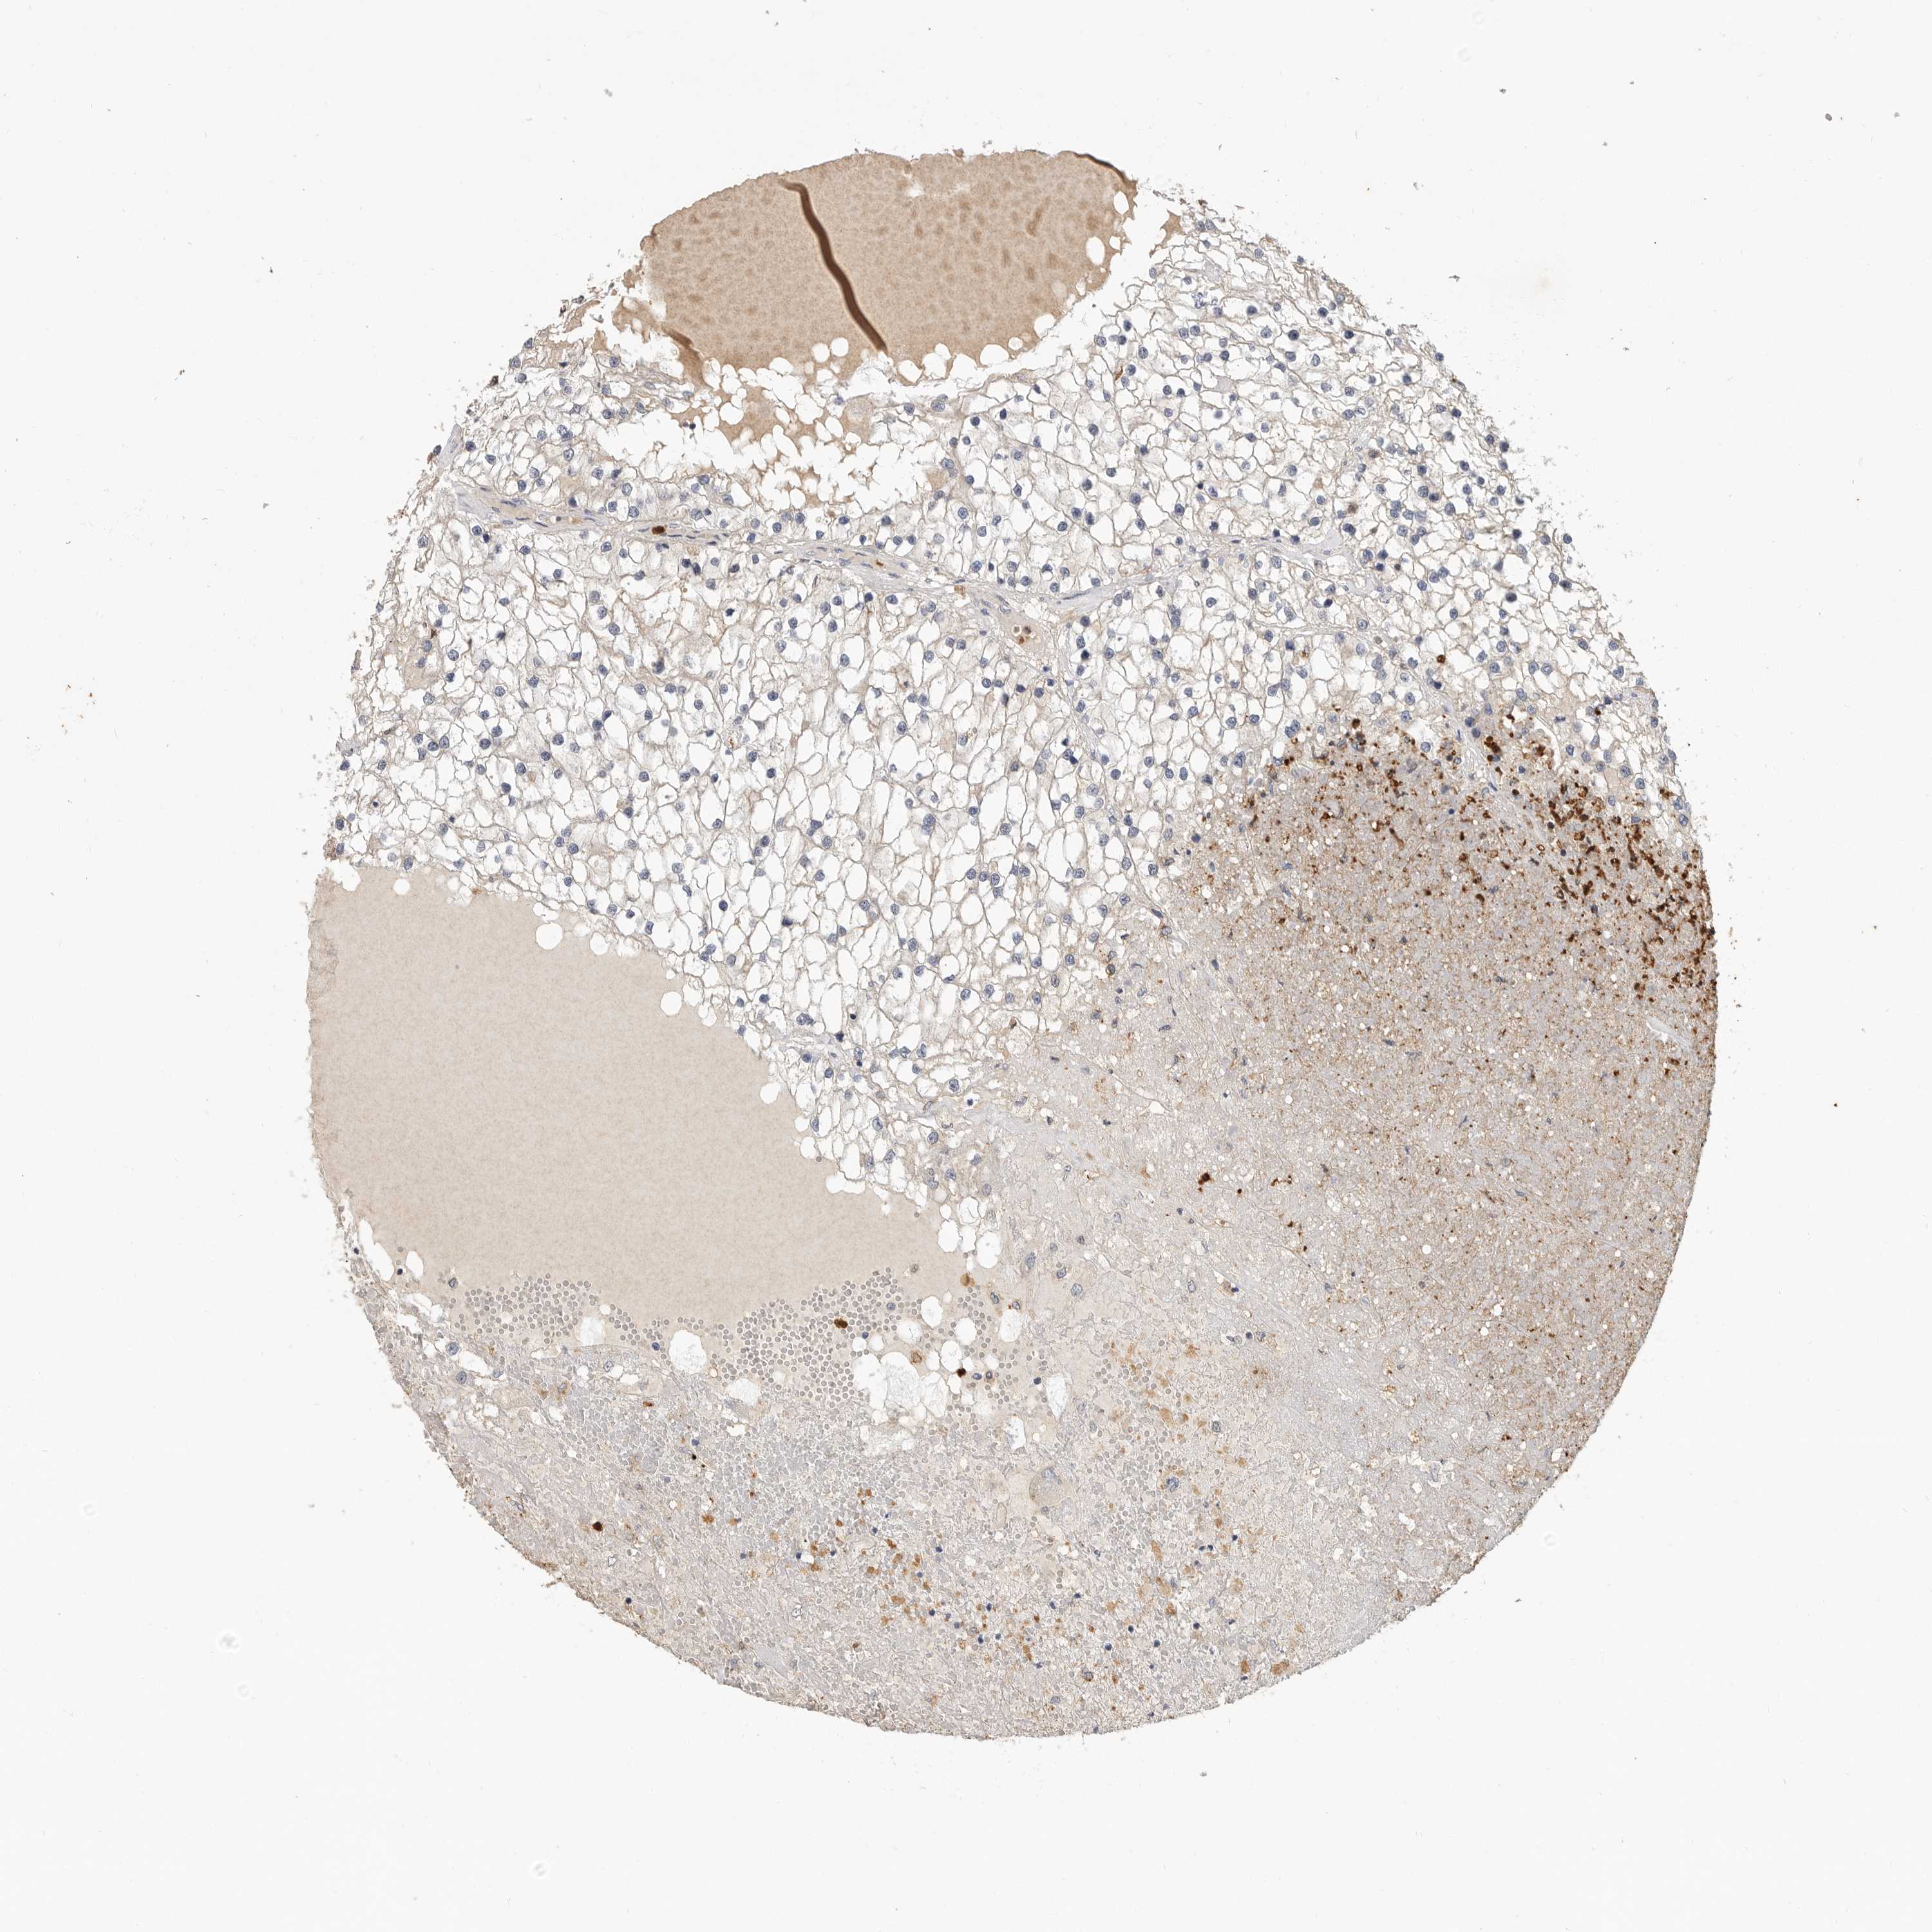

KIDNEY RENAL CLEAR CELL CARCINOMA (VALIDATION) - Interactive survival scatter ploti

The Survival Scatter plot shows the clinical status (i.e. dead or alive) for all individuals in the patient cohort, based on the same data that underlies the corresponding Kaplan-Meier plots. Patients that are alive at last time for follow-up are shown in blue and patients who have died during the study are shown in red.

The x-axis shows the expression levels (FPKM) of the investigated gene in the tumor tissue at the time of diagnosis. The y-axis shows the follow-up time after diagnosis (years). Both axes are complimented with kernel density curves demonstrating the data density over the axes. The top density plot shows the expression levels (FPKM) distribution among dead (red) and alive patients (blue). The right density plot shows the data density of the survived years of dead patients with high and low expression levels respectively, stratified using the cutoff indicated by the vertical dashed line through the Survival Scatter plot. This cutoff is automatically defined based on the FPKM cutoff that minimizes the p-score. The cutoff can be changed by dragging the vertical line or by entering a cutoff value in the square labeled "Current cut-off".

Under the Survival Scatter plot the p-score landscape (black curve; left axis) is shown together with dead median separation (red curve; right axis). Dead median separation is the difference in median mRNA expression between patients who have died with high and low expression, respectively. It is calculated as follows: median FPKM expression of dead patients with high expression - median FPKM expression of dead patients with low expression. This is intended to aid the user in visually exploring custom cutoffs and the associated p-scores and dead median separation.

Individual patient data is displayed and can be filtered by clicking on one or more of the category buttons on the top of the page. Categories describing expression level and patient information include: high, low, alive, dead, female, male and tumor stages. The scale of the x-axis can be toggled between linear and log-scale by clicking on the "x log" button. Mouse-over function shows TCGA ID, patient information and mRNA expression (FPKM) for each patient.

& Survival analysisi

Kaplan-Meier plots summarize results from analysis of correlation between mRNA expression level and patient survival. Patients were divided based on level of expression into one of the two groups "low" (under cut off) or "high" (over cut off). X-axis shows time for survival (years) and y-axis shows the probability of survival, where 1.0 corresponds to 100 percent.

LTBR is not prognostic in Kidney Renal Clear Cell Carcinoma (validation)

Best expression cut offi

Based on the FPKM value of each gene, patients were classified into two groups and association between prognosis (survival) and gene expression (FPKM) was examined. The best expression cut-off refers the FPKM value that yields maximal difference with regard to survival between the two groups at the lowest log-rank P-value. Best expression cut-off was selected based on survival analysis .

When clicking on this number, the vertical dashed line indicating cut-off, the interactive survival plot, and the Kaplan-Meier curve will be adjusted to show results based on the best expression cut-off.

: 133.14

TCGA RNA samplesi

RNA-seq data is reported as average FPKM (number Fragments Per Kilobase of exon per Million reads), generated by the The Cancer Genome Atlas (TCGA) .

Normal distribution across the dataset is visualized with box plots, shown as median and 25th and 75th percentiles. Points are displayed as outliers if they are above or below 1.5 times the interquartile range. FPKM values of the individual samples are presented next to the box plot.

Average pTPM 117.1

Number of samples 100